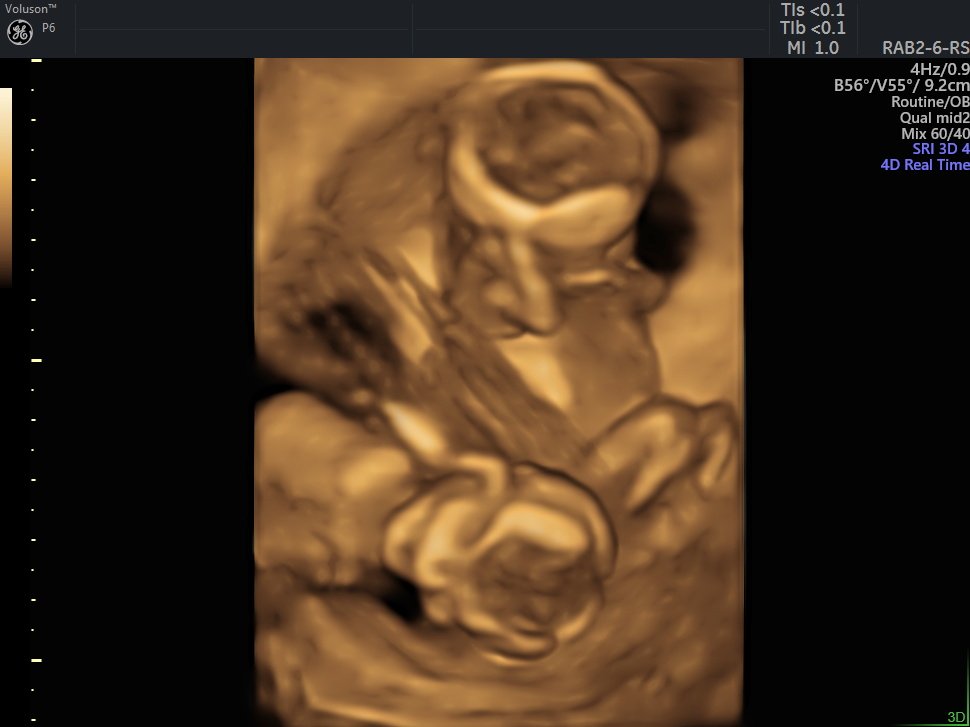

4 Boyutlu (Renkli) Ultrason ve Doppler Ultrasonografi

4 D Ultrasonografi